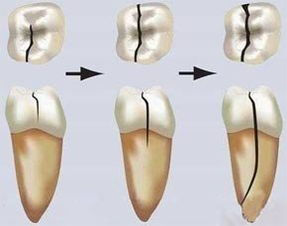

牙隐裂:指牙冠表面的非生理性细小裂纹,常不易被发现。牙隐裂的裂纹常深入到牙本质结构,是牙齿敏感及牙痛的原因之一。牙齿上的这个小小裂纹如果没及时发现并治疗,那么它最终可能导致牙齿折裂,甚至最终造成失牙。

牙齿虽然十分坚硬,但是牙结构也有其薄弱的环节,这些薄弱环节不仅本身抗裂强度低,而且是牙齿承受正常力时,应力集中的部位。当病理性磨损过高,就会形成创伤性力,使窝沟底部的釉板向牙本质方向加深加宽,这就是隐裂纹的开端。

④当裂纹已涉及龈下、根尖周组织或牙根已纵裂开时,就只好拔除患牙了。